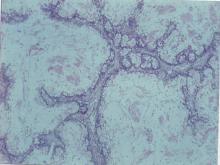

大體解剖檢查,除一隻公鼠外,其他五隻公母鼠皆無異常。此公鼠唯一肉眼病變為腹腔內距迴盲瓣約18 cm處的空腸有一段球狀脹大,大小直徑2.2 cm。腸管橫切面呈黃黑與透明似軟骨碎感固體長出團塊(mass),其間摻雜有黏稠,糊樣腸腔內容物,腫瘤表面 腸腔只餘1.5 mm寬空隙,可容前端腸內容物通過。其他內臟皆正常。 三、 組織病變: 腫瘍團塊在低倍顯微鏡鏡檢下幾乎佔據所有腸腔,只剩下少許空隙。除腸內容物炎症壞死物質外,並含有很多絨毛膜樣細菌團塊(bacterial matts)。腫瘤由許多大小不同增生的粘液腸道管腺(mucinous intestinal glands)而成,有的發育不全(dysplastic),有的含大量粘液呈囊包(mucinous cysts)的構造(圖1)。大部分增生腸管腺為乳突樣增生(papillary growth)(圖2,3),有的為修長管狀腸腺增生,腔內亦含有些純紅色到淡藍色鹼性粘液。很多已分化成杯狀細胞,或圓柱形,或立方形、核多型,位於基底膜上。腫瘤細胞分裂很少見。特別染色PAS與Alcian blue(pH 1.0)呈陽性。腫瘤外圍靠近正常腸黏膜處的腫瘤細胞核濃染(hyperchromatic),並侵入腸壁粘膜下層增生。腫瘤細胞內為間質組織增生,並形成有類骨質異化(osteoid metaplasia),骨組織外圍可見有許多蝕骨細胞(osteoclasts)(圖4)。此病例並無癌細胞轉移現象。 四、 診斷: 大鼠黏液性小腸腺癌(Spontaneous Intestinal Mucinous Adenocarcinoma in a SD Rat) 五、 討論: 1.